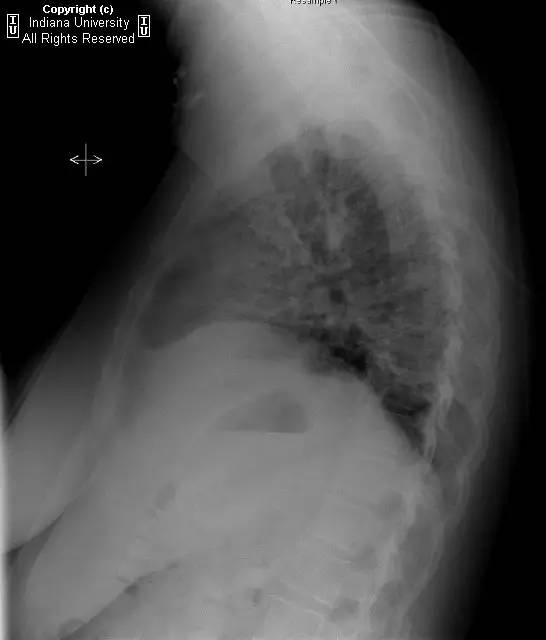

【影像学表现】胸片示双肺纹理增多,间质性透光度减低。无局灶性病变,气胸或胸腔积液。心脏及纵膈轮廓正常。CT示双肺弥漫间质性病变,累及所有肺叶,以下叶为著。肺间质增厚,结构扭曲,牵拉性支气管扩张,外周呈蜂窝状改变。肺动脉增粗,符合肺动脉高压。